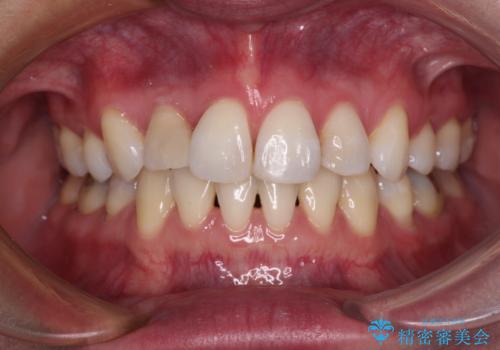

治療期間の目安は3年~3年半でしたが、咬み合わせにより上顎のスペースがなかかな閉じきらず、治療期間が長期化してしまいました。

期間はかかったものの、口元の張り出し感や歯のデコボコが解消され、患者様には大変満足していただけました。